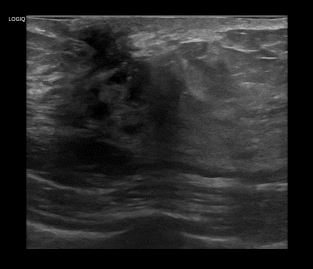

상기환자 우측 만져지는 멍울로 정밀검사위해 내원하신 50대 여성분으로

우측유방 혹 총조직검사 시행해 유방암 진단되었습니다